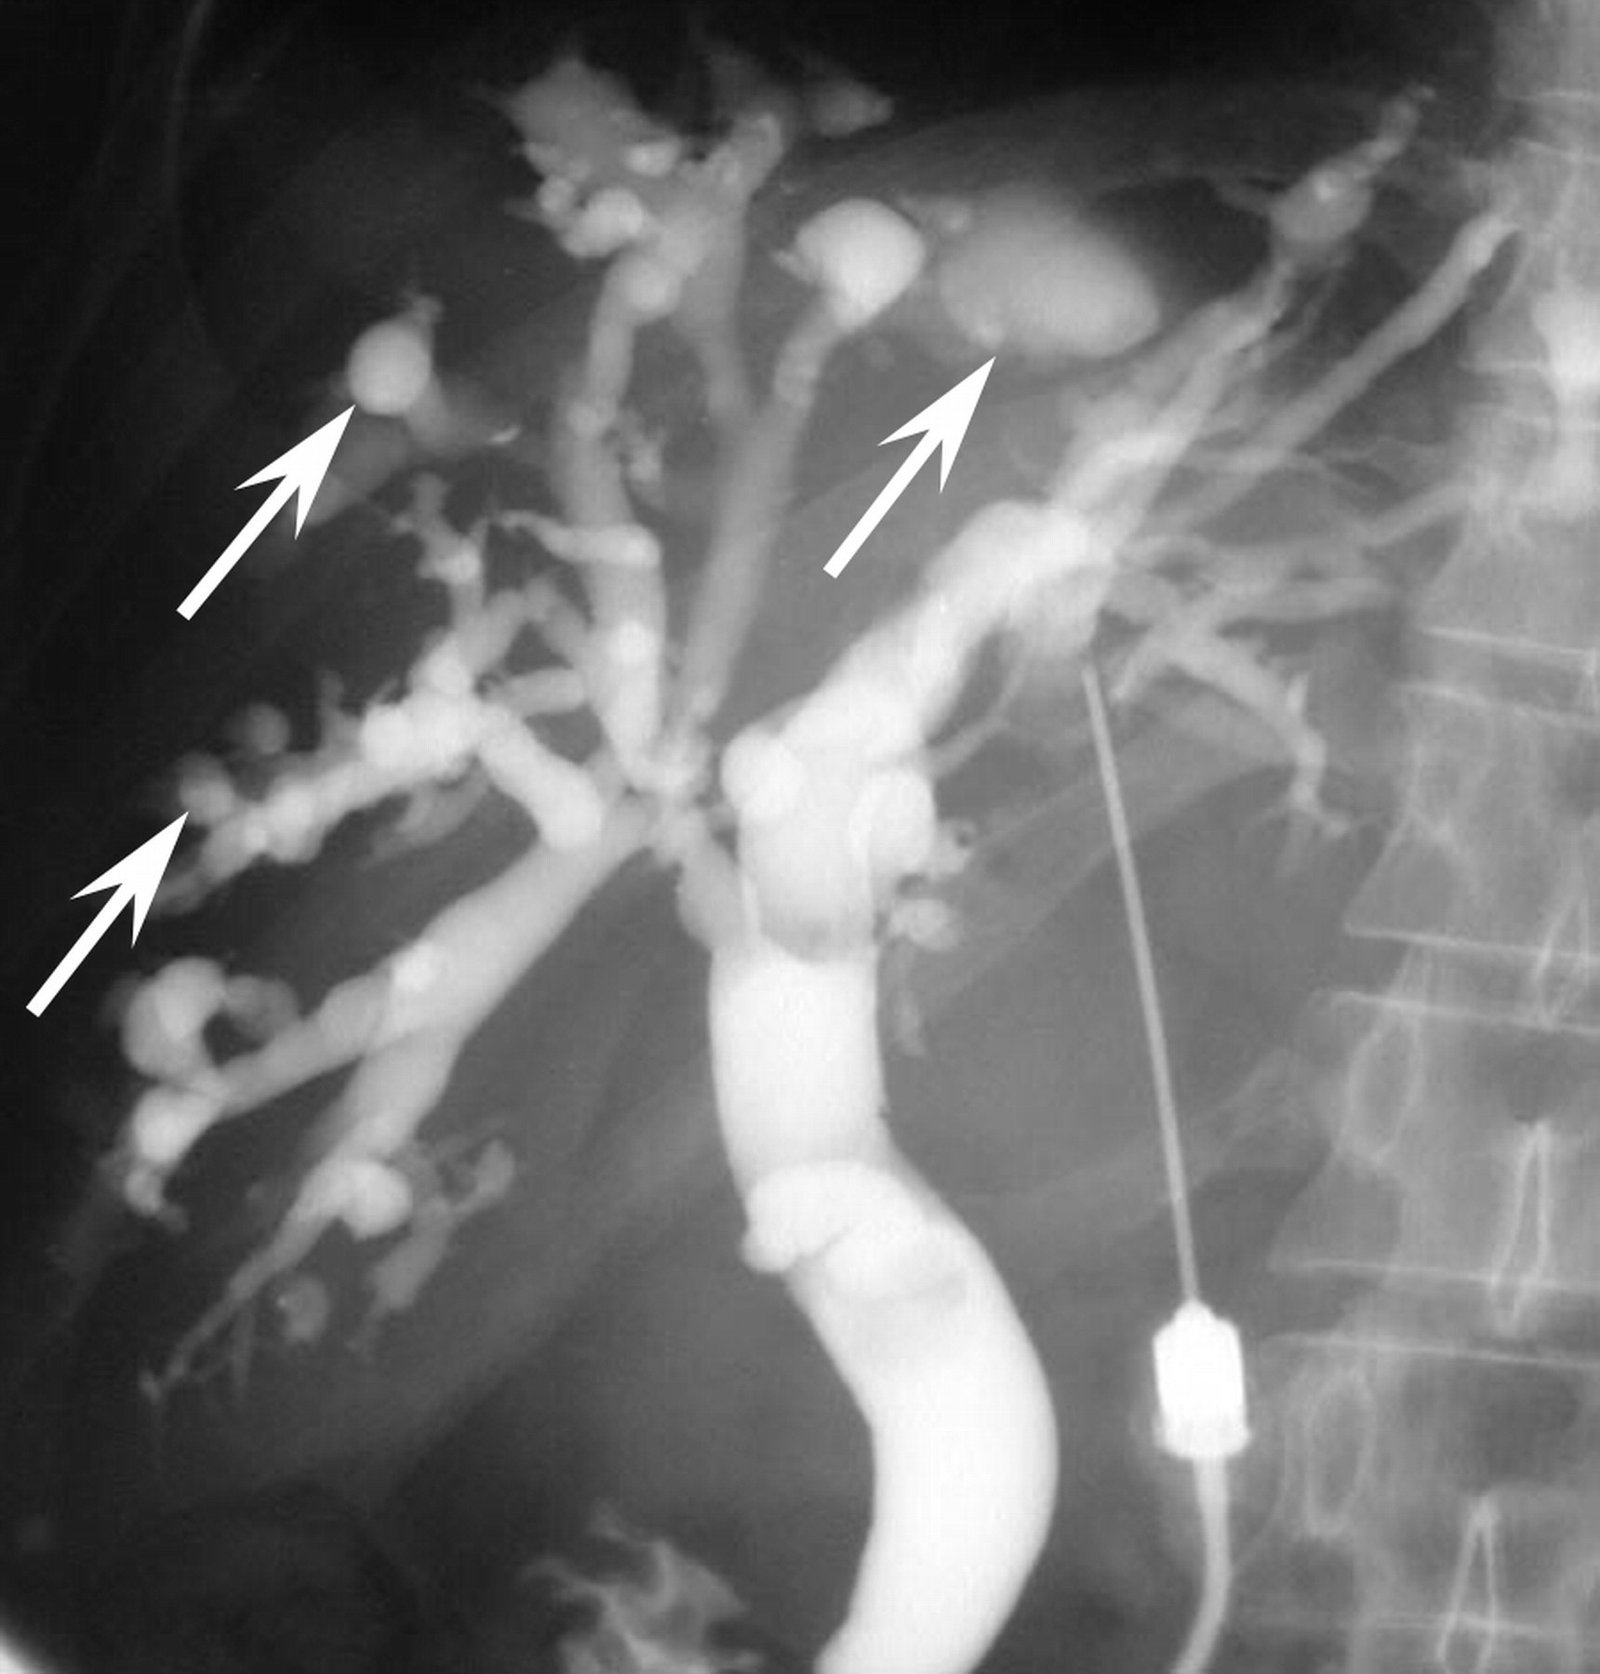

Seqment III bypass əməliyyatı

Tərifi:

• Obstruktiv sarııqda, qaraciyər qapısı patoloji proses ilə tutulan zaman intrahepatik öd yolu ilə bağırsaq arasında qoyulan anastomoza deyilir.

• Qaraciyər qapısında yerləşən bədxassəli proseslər zamanı xəstələrin 80% palliativ əməliyyatlar aparılmaqdadır (metastaz və ya lokal yayılması səbəbi ilə)

Məqsəd:

• Uzun müddətli öd axınını bərpa edilməsi və bununla xəstələrin əziyyət çəkdikləri simptomlardan azad edilməsidir (qaşınma, xolangit, ağrı, sarılıq)

• Bu tip xəstələrin yaşama keyfiyyətini artırması

Göstərişlər:

• Rezeksiya oluna bilməyən ümumi öd axarının bədxassəli obstruksiyası (daha çox öd kisəsi karsinomalarında)

• Uzun məsafəli xoşxassəli strikturaları  (ümumi öd axarına girilməsi mümkün olmayanda)

• Biliar xaçanın tam obliterasiyası zamanı (hilar xolangiokarsinomalarda)

Texnika:

• Ümumi anestaziya altında aparılır

• Kəsik tərs L və ya sağ subkostal

• I mərhələ - III və IV seqmentlər arası sahənin açılması

• Ümumi öd axarının ekspozisiyası (hepatoduodenal bağın disseksiyası)

• Seqment III axarının identifikasiyası

• Bilioentral anastomozun qoyulması